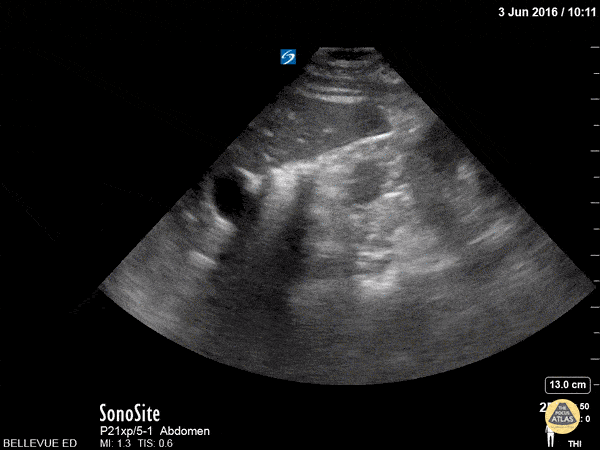

Renal/GU - Kidney Transverse

This is a clip of the right upper quadrant structures in transverse view. The kidney has a hyperechoic center made up of the renal pelvis and calyces, surrounded by a hypoechoic cortex similar in echogenicity to the liver (seen to the left of the screen). Within the liver we see prominent anechoic vasculature. A dark rib shadow moves across the field as the sonographer fans. Hannah Kopinksi and Dr. Lindsay Davis - NYU Emergency Medicine